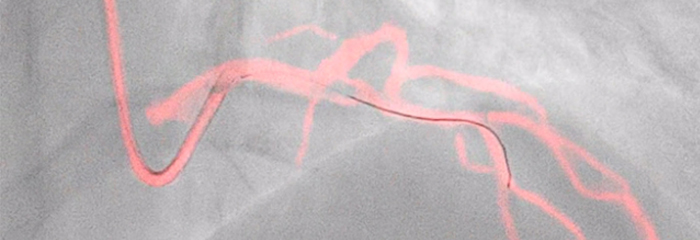

See clearly, guide confidently — Dynamic Coronary Roadmap

Automatic, real-time navigational guidance designed for procedure efficiency in complex PCI interventions without changing current standard workflow.You are about to visit a Philips global content page